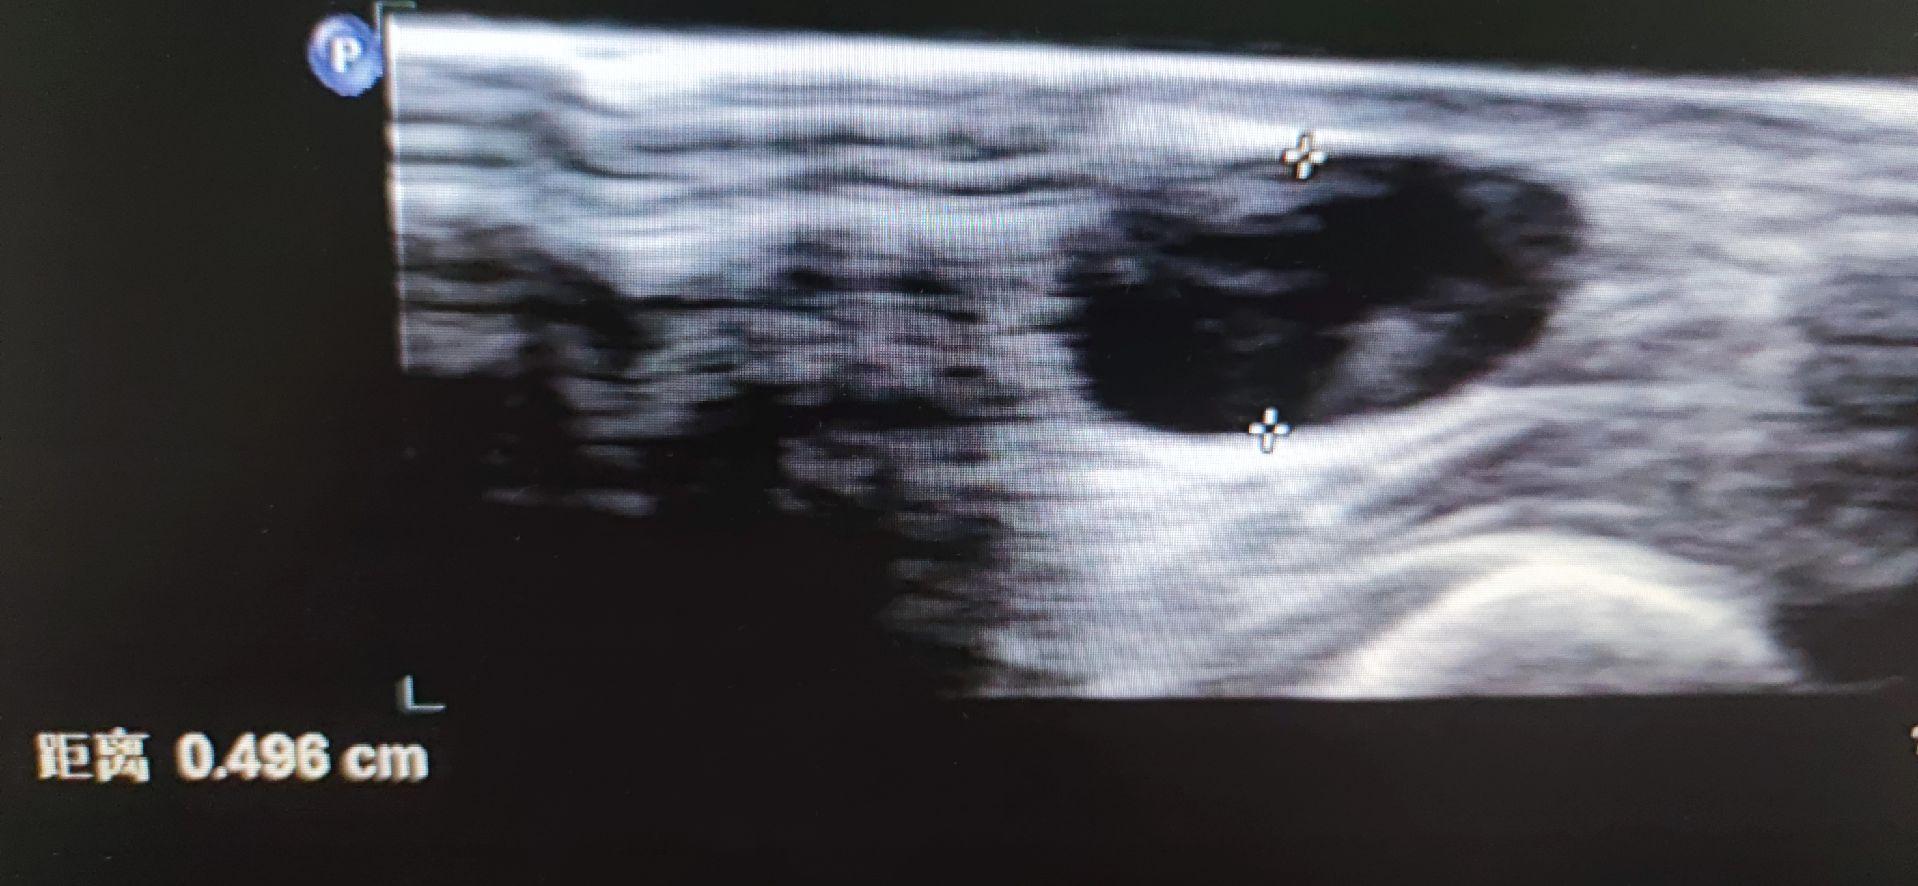

自体动静脉内瘘超声。AVF透析造瘘术前上肢血管超声前臂透析内瘘术后成熟度超声

自体动静脉内瘘超声。AVF 透析造瘘术前上肢血管超声 前臂透析内瘘术后成熟度超声